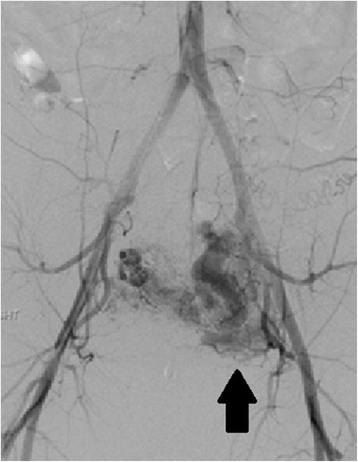

Left uterine artery arterio-venous malformation (AVM) by pelvic angiogram. This patient had undergone an uncomplicated ultrasound-guided D&C for a 10 week size cesarean scar ectopic pregnancy 2 months prior to presentation with vaginal bleeding and diagnosis of a left uterine artery AVM (arrow). The AVM was embolized with coils, but the patient required emergent hysterectomy for hemorrhage